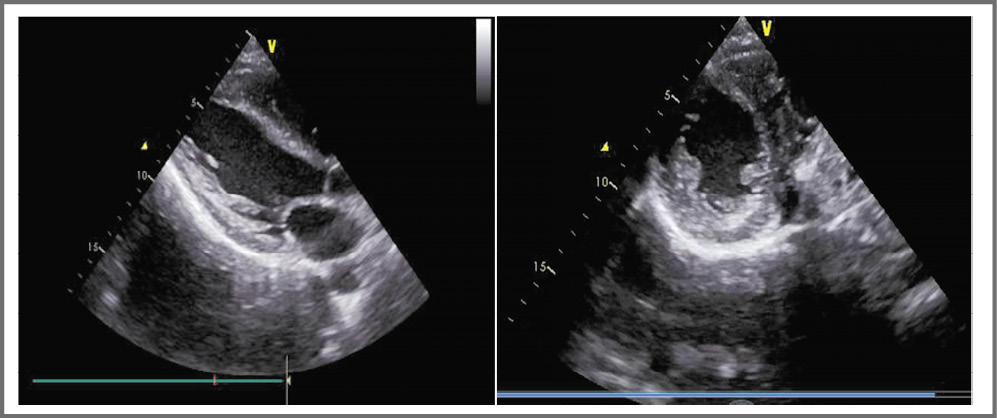

Эхокардиографическое исследование выявило существенные изменения, характерные для БФ: гипертрофия ЛЖ, толщина задней стенки ЛЖ в диастолу составила 13 мм, толщина межжелудочковой перегородки в диастолу – 13 мм, индекс массы миокарда – 127 г/м2 (рис. 3). Глобальная сократимость ЛЖ сохранена (фракция выброса по Simpson – 60%), отсутствуют нарушения локальной сократимости и признаки диастолической дисфункции желудочков; крупные сосуды, клапанный аппарат и перикард – без особенностей. Данные допплеровской кардиографии: митральная регургитация 1-й степени, трикуспидальная регургитация 1-й степени. Давление в легочной артерии не изменено (17 мм рт. ст.). При проведении исследования обращала на себя внимание повышенная эхогенность миокарда (см. рис. 3).

Рис. 3. Трансторакальная эхокардиография больного Б.: гипертрофия стенки ЛЖ.

Fig. 3. Transthoracic echocardiography of Patient B.: left ventricular hypertrophy.